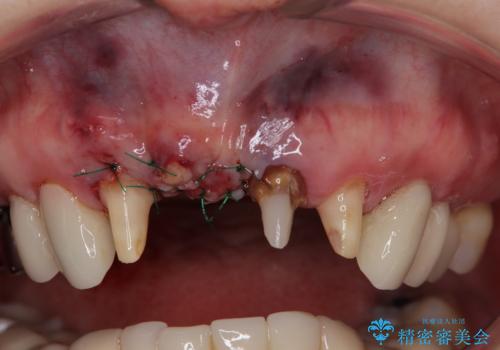

前歯のインプラントは埋入されたポジションが望ましい位置ではなく、インプラントを活用して段差を回収することは不可能と判断し、歯肉移植によりインプラントを隠して、ブリッジにて歯肉ラインを整えることとしました。

臼歯部の治療も必要と判断されましたが、前歯部を中心とした審美領域をオールセラミッククラウンによる補綴治療を行うこととしました。

帰国時のみの治療であったため、治療期間は長くなりましたが、最小限の来院回数で、気になっていた前歯をきれいに整えることができました。